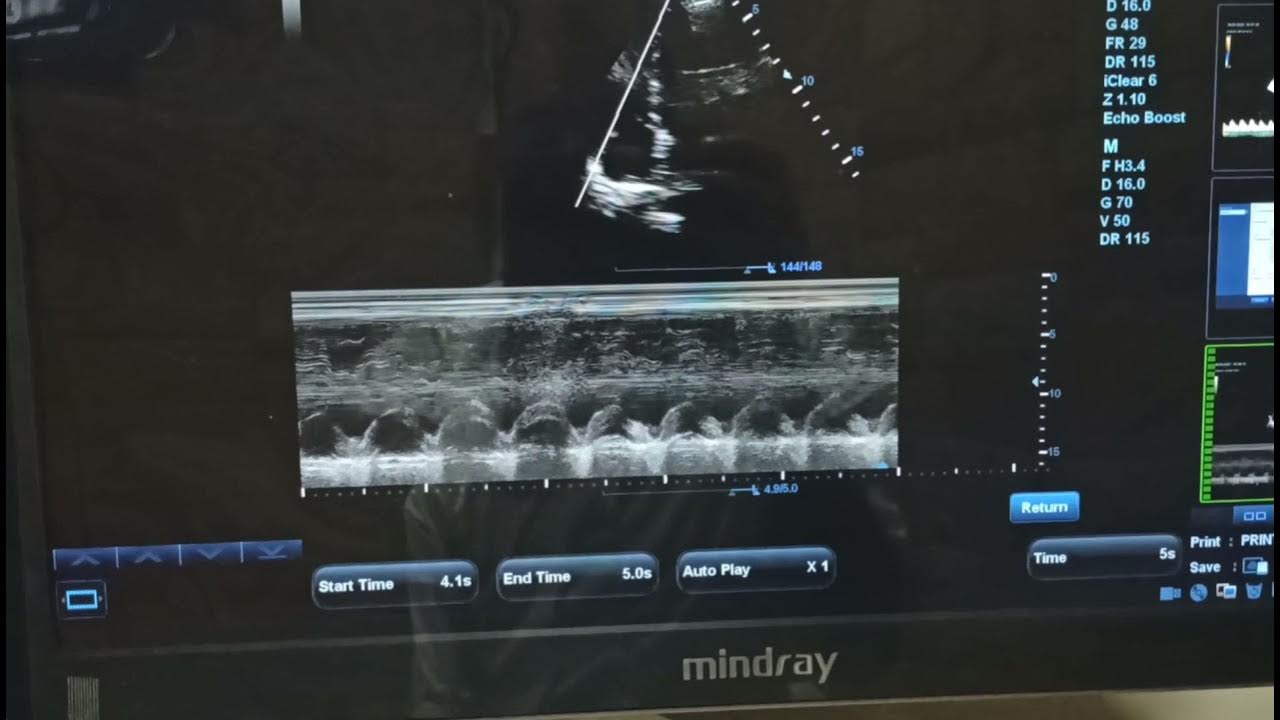

From www.youtube.com

Mmode tracing of MAPSE & TAPSE YouTube Where To Measure Tapse The ultrasound view to assess tapse can be achieved in the vast majority of patients by emergency physicians, who can then measure tapse quickly and reliably. Applied to the right patient population, tapse is highly sensitive for rv dysfunction. The end point was cvd. And how to measure it?. This is a parameter we use to assess the right ventricular. Where To Measure Tapse.